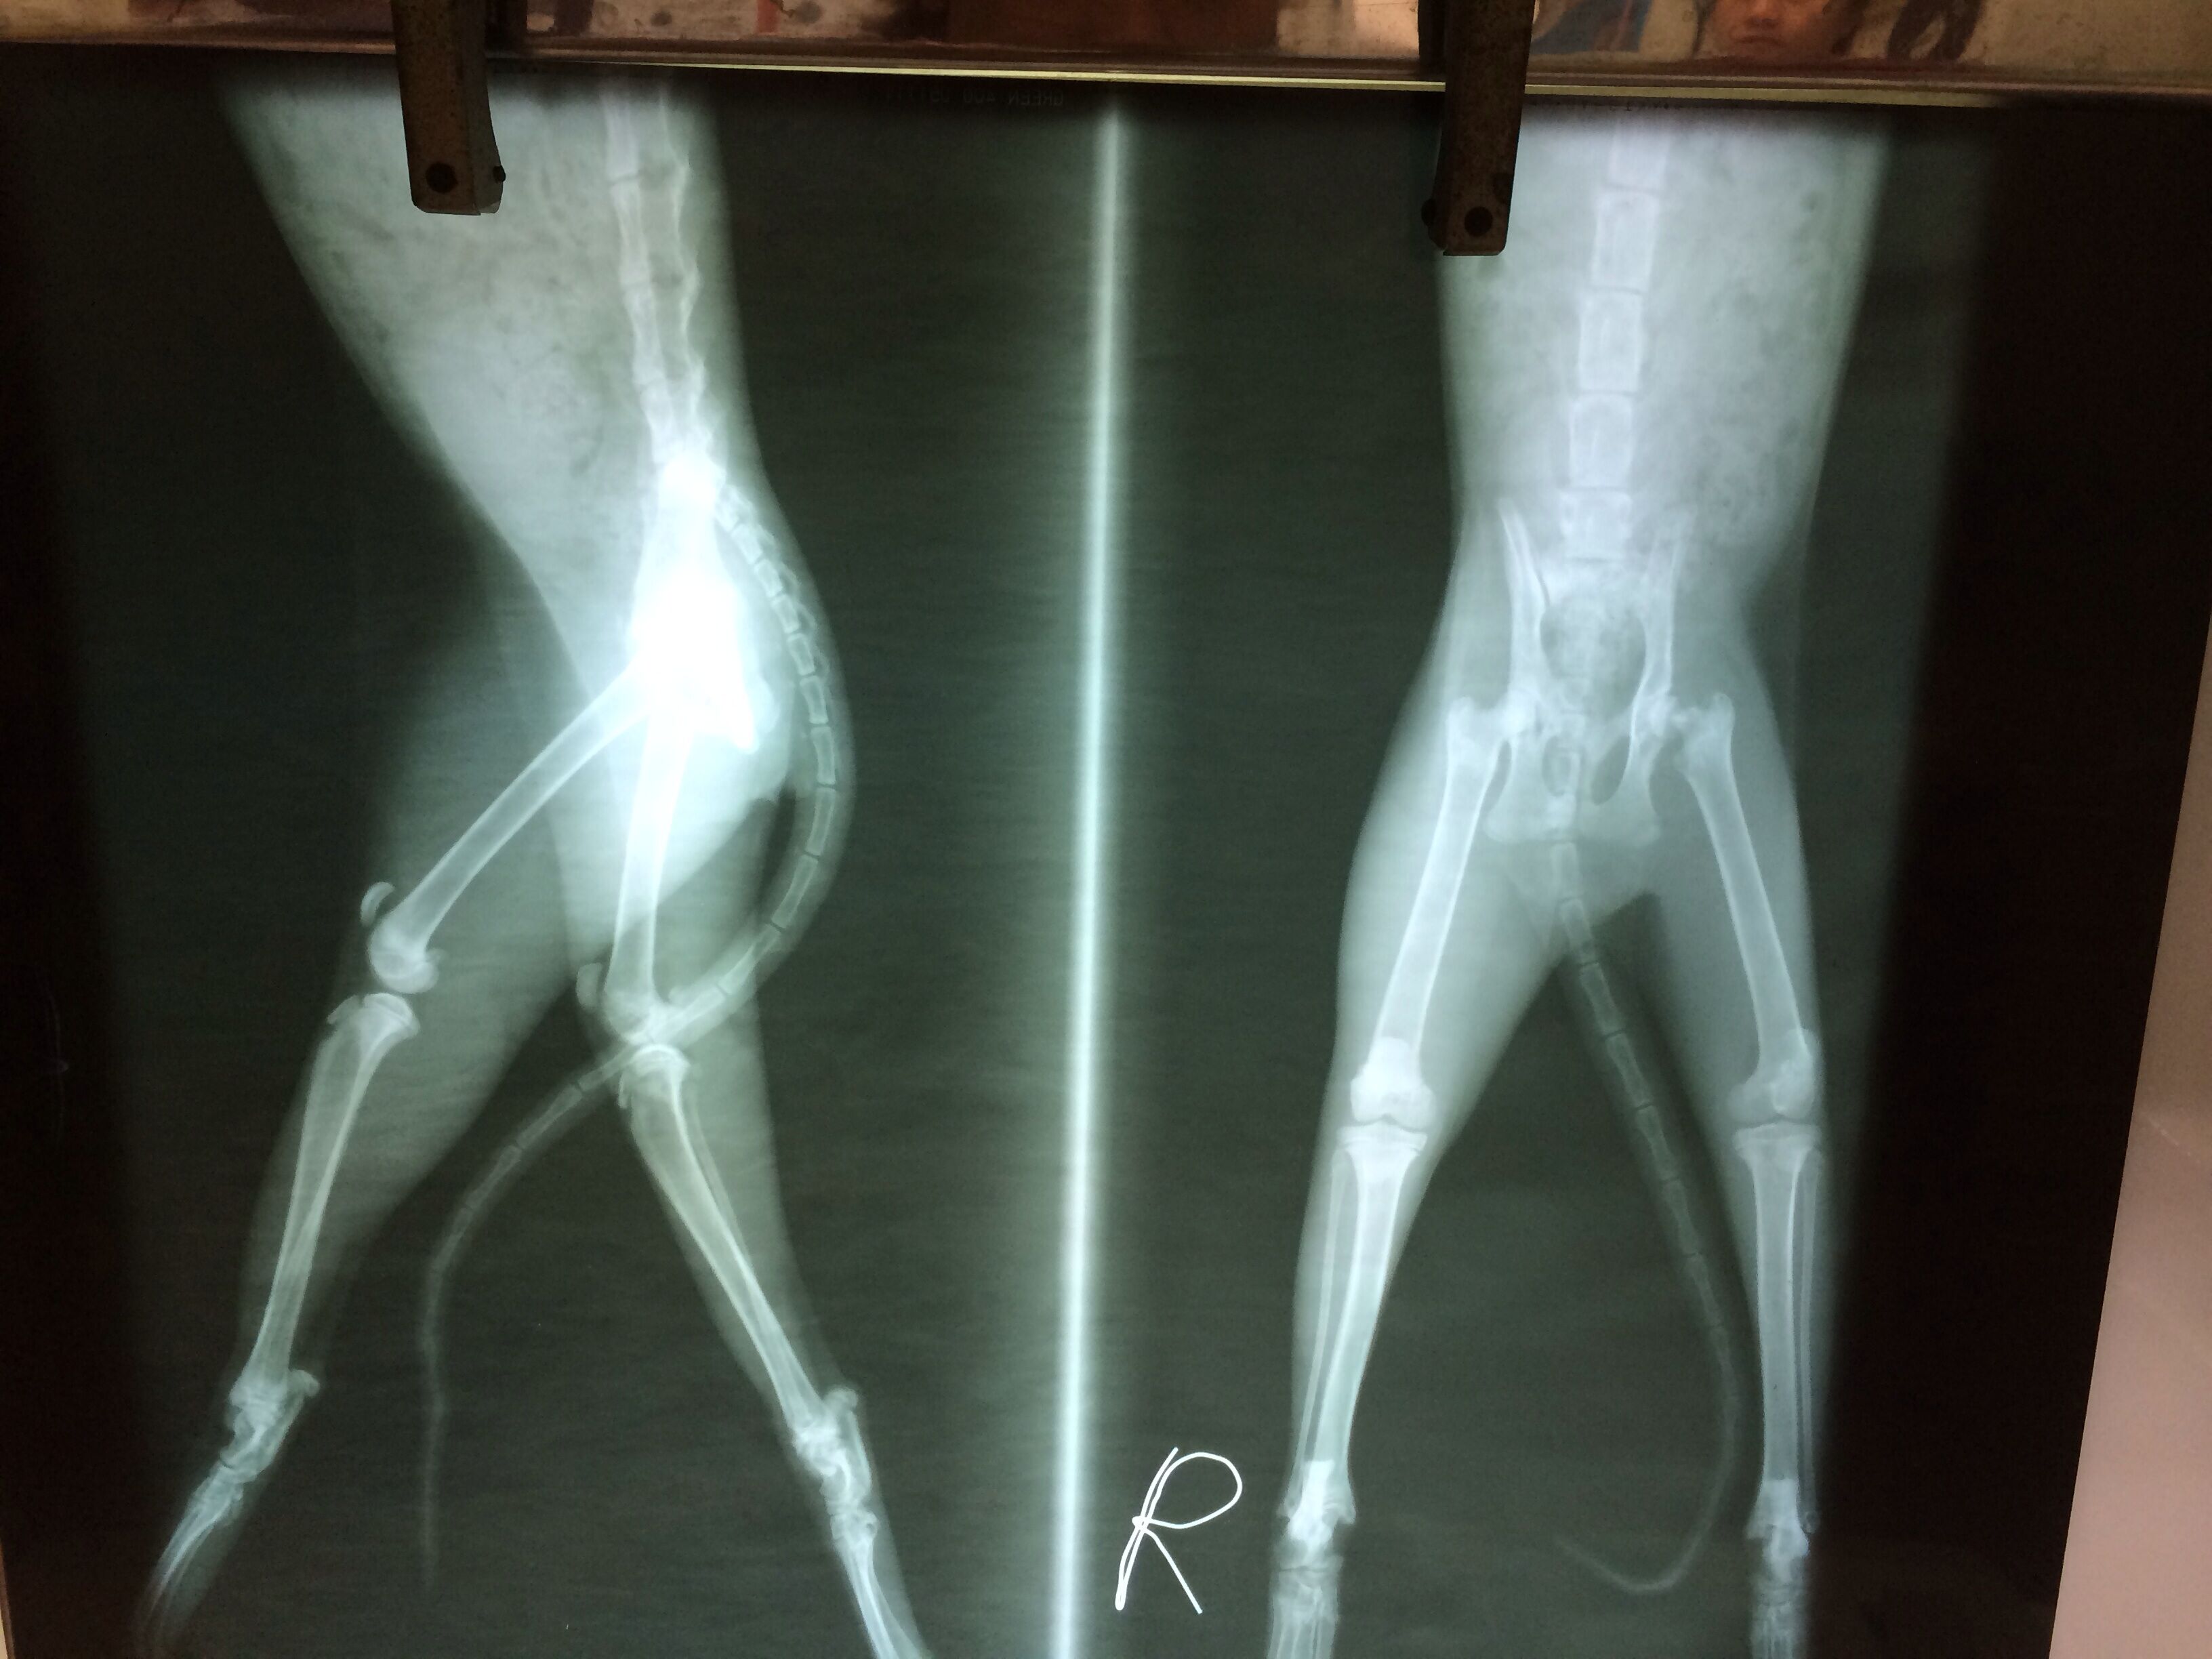

- 編號: 3949

主題: 高雄小貓被機車撞到骨折 申請者姓名: Sexson Dai 花色: 申請日期: 2014-02-09 12:00:12 申請者部落格: 申請者臉書網址: 所在縣市/合作醫院: 高雄市/新德民動物醫院 治療費用: 13550元 需求人數: 15人 已結案 (2014-03-24 18:14:14) 報名人員: 彭小花(已付款)、Patrick x2(已付款)、Kristy Lee(已付款)、Eva Tsai、烙跑專用(已付款)、徐米奇(已付款)、Melody Wu(已付款)、julie lee(已付款)、橙小瑩(已付款)、Hsiao-Peng Su(已付款)、孟孟 x2(已付款)、Meng-Chen Tseng(已付款)、小娃(已付款)、佳淳(已付款)、 候補人員: Bagel Li、 動物病情說明: 貓咪在本月大年初三和志工朋友去吃早餐遇到的,走路非常異常是用蹬的,詢問早餐店老闆說一個星期前被機車撞到,前腳有明顯外傷,指甲已外翻,後腳雖無明顯外傷但後腳無力,無法正常行走和跳,當下就和另一名志工朋友就請老闆幫我們留意,準備誘補小貓,小貓已確定是浪貓,因為貓媽媽會帶他們來向早餐店老闆討食,我於今天民國103年2月4日下午三點左右送到高雄德民動物醫院,醫生初步診斷左後腳有照X光確定斷掉,右前腳掌指甲外翻,手術費及醫療費醫生估約10000左右 動物近況說明: 小貓術後身體狀況正常,恢復的不錯,我會將他帶回家中途療養,直到好了,在將小雪找個好主人